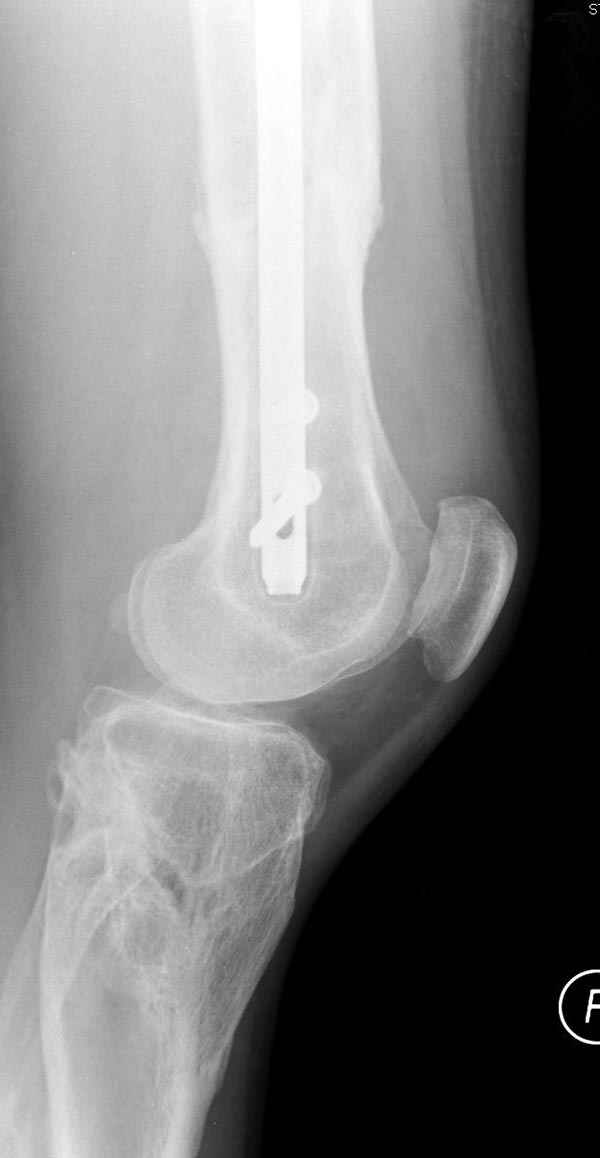

Замена реконструктивного штифта “Custom made Nail” с антибиотиком (рис №5, №6),

после промывки канала с рассверливанием внутреннего кортекса, через 4 недели антибиотический штифт удалили, оспалителный процесс остановлен и бедро сросся.

Мы не дождались “Happy End”, у больного IQ в пределах 70%, через 6 месяцев вернулся после небольшой травмы, споткнувшись получил перелом

того же бедра (рис №7).